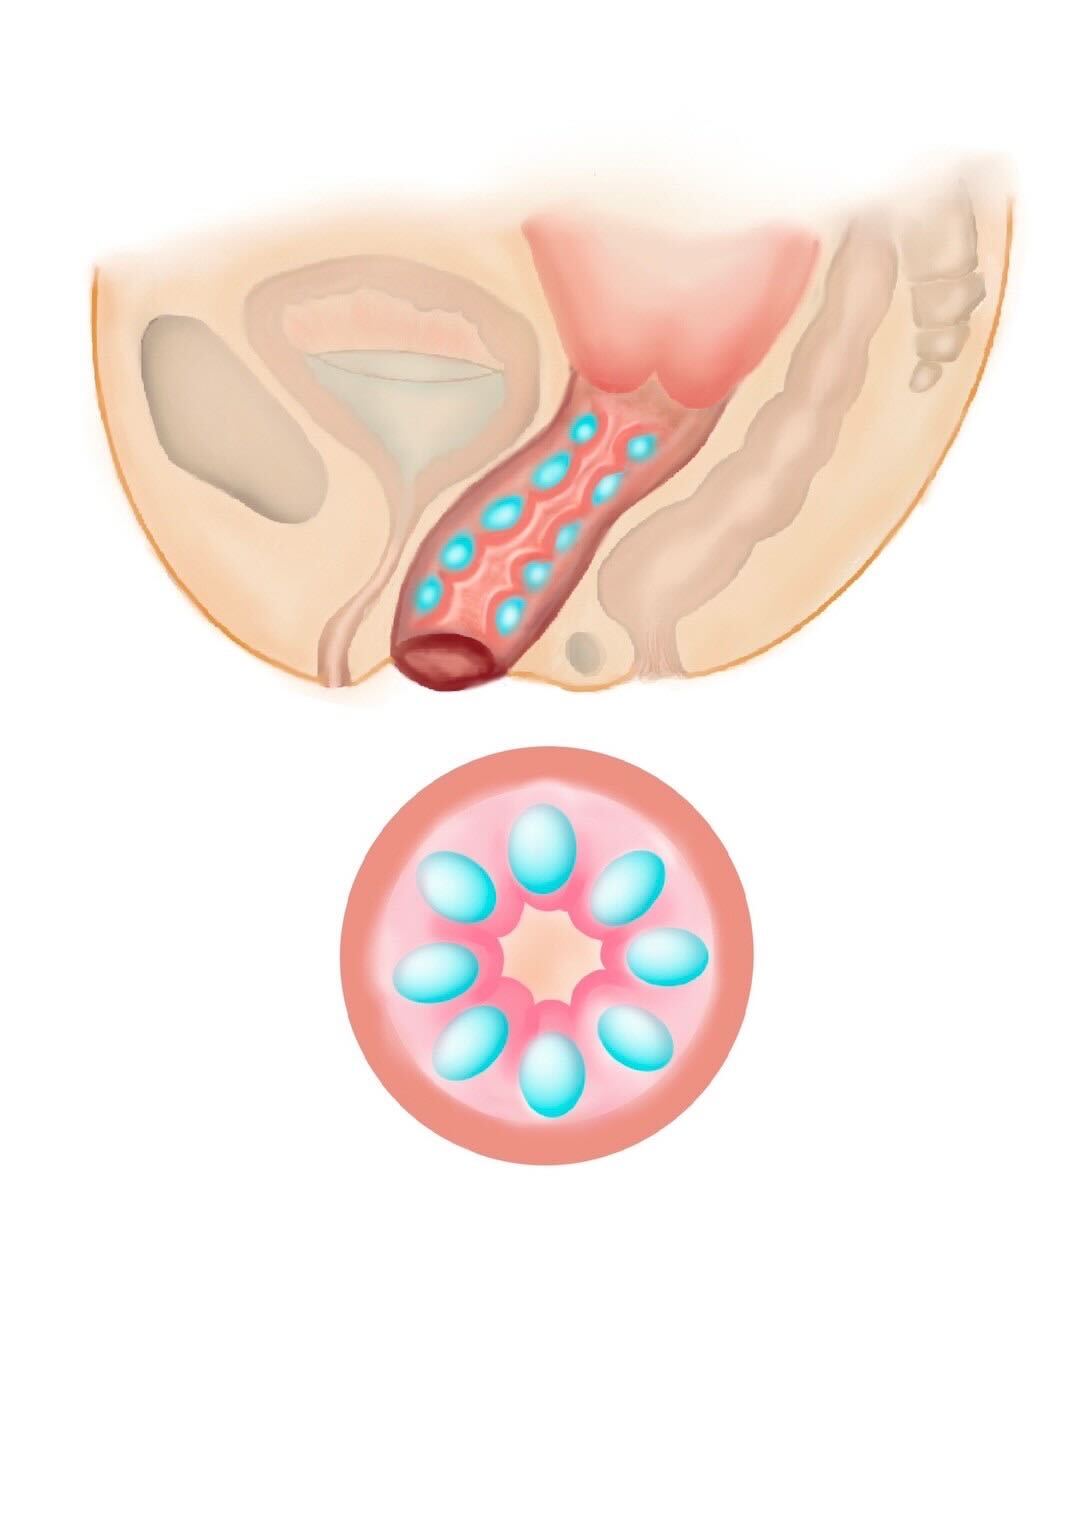

Type01 みみず千匹

みみず千匹

かずのこ天井

③ 多層注入(バランスのとれた名器形成)

膣の内〜外側にかけてヒアルロン酸をバランスよく注入する方法で、膣のハリと潤いを向上させ、より自然な仕上がりを目指す注入方法です。

膣のフィット感と潤いを同時にサポートしたい方に適しています。

④ 立体層状注入(名器形成を目的とした施術)

膣内の構造を立体的に整え、締まり感と性感向上を目的とした施術で、ヒアルロン酸を膣内に立体的に注入することで、ボリュームを調整し、より高い密着感やフィット感を目指します。

より強い締まり感やパートナーとの密着感を求める方に適しています。

また、ご希望に応じて、巾着、タコつぼ、数の子天井、俵締め、みみず千匹などと称される施術方法にも対応しております。